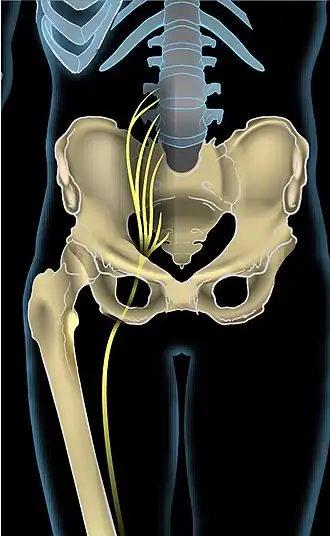

| Anterior view showing the sciatic nerve going down the right leg | |

Sciatica is pain going down the leg from the lower back.[1] This pain may extend down the back, outside, or front of the leg.[3] Onset is often sudden following activities such as heavy lifting, though gradual onset may also occur.[5] The pain is often described as shooting.[1] Typically, symptoms occur on only one side of the body;[3] certain causes, however, may result in pain on both sides.[3] Lower back pain is sometimes present.[3] Weakness or numbness may occur in various parts of the affected leg and foot.[3]

The sciatic nerve comprises nerve roots L4, L5, S1, S2, and S3 in the spine.[26] These nerve roots merge in the pelvic cavity to form the sacral plexus and the sciatic nerve branches from that. Sciatica symptoms can occur when there is pathology anywhere along the course of these nerves.[27]